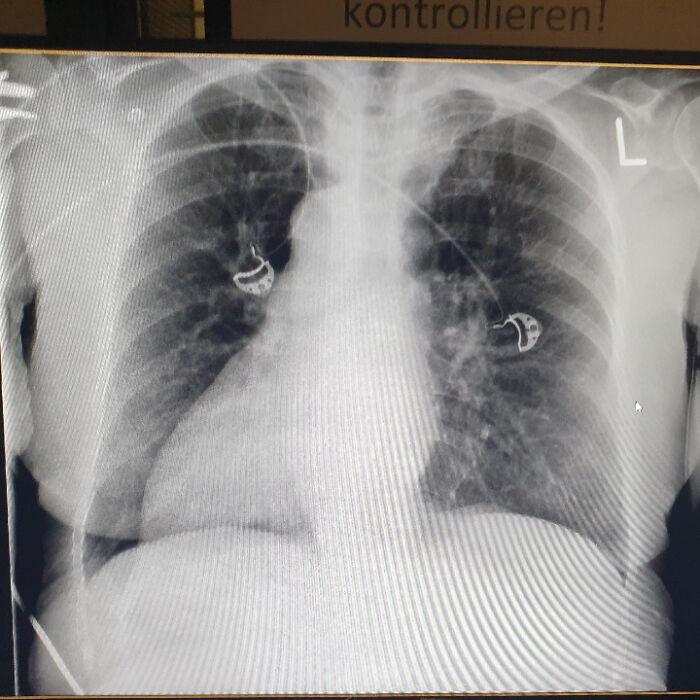

W kursie sekcyjnym kadawer miał wszczepiony rozrusznik, który regularnie aktywował się i brzmiał jak syrena karetki. Przy otwarciu klatki piersiowej okazało się też, że serce jest tak powiększone, że praktycznie zmieściło lewą płucną tkankę pod sobą — niezwykły, ale edukacyjny widok.